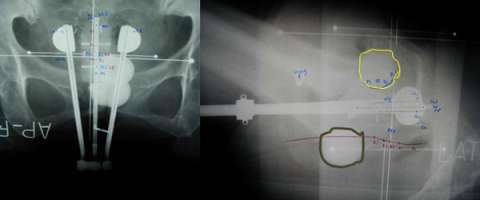

Here is an axial CT scan slice of an actual patient with her bladder full on the left and her bladder empty on the right. You can see that with the bladder (yellow) empty that additional bowel falls within the pelvis and that the marker seeds (red) are in a different place (also in part due to increased air in the rectum (brown). This example demonstrates the importance of daily image guidance and making sure that your bladder is consistently full during the course of your treatment.

CT Scan